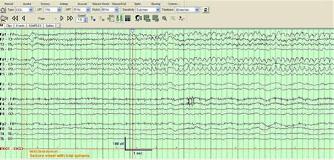

Rationale: Lacosamide is a novel AED approved for the treatment of partial epilepsy. Anecdotal reports have suggested efficacy in patients with status epilepticus or acute repetitive seizures though such cases are relatively few in the published literature.Methods: We report three patients who presented with either acute repetitive seizures or with NCSE who were refractory to conventional therapy but responded rapidly to intravenous lacosamide. Continuous video-EEG monitoring data was reviewed and correlated with the response to lacosamide.Results: A 60 year old man with left frontotemporal anaplastic astrocytoma was admitted for ictal aphasia refractory to appropriate doses of valproate, pregabalin and levetiracetam. EEG showed almost continuous left hemispheric electrographic seizures (Figure 1). After receiving 100 mg of intravenous lacosamide and initiation of maintenance therapy there was resolution of aphasia and the ictal pattern over a 24 hour period. A 56 yr old man with left intraparenchymal and subarachnoid hemorrhage developed worsening confusion followed by a GTC seizure. He was noted to have continuous electrographic seizures emanating from the left hemisphere and were associated with persistent confusion and orofacial automatisms. After failing to improve with adequate doses of phenytoin, 300 mg intravenous lacosamide was given as a load followed by 100 mg twice daily. Within twelve hours by EEG criteria his seizure frequency declined to < 75% and by 24 hours resolved completely. A 84 year old man with history of right hemispheric stroke and mild cognitive impairment was admitted for confusional episodes. He was noted to have electrographic seizures originating from either hemispheres associated with staring and dysphasia. After failing to respond to appropriate doses of intravenous Levetiracetam, to avoid sedation intravenous Lacosamide was introduced at 100 mg twice daily that resulted in rapid reduction of seizure frequency and eventually complete resolution of seizures within 36 hours. Subsequent inadvertent discontinuation of lacosamide as an outpatient resulted in recurrence of seizures, however, reintroduction of Lacosamide resulted in excellent seizure control. Conclusions: Based on our results, in patients with refractory acute repetitive seizures or non-convulsive status epilepticus lacosamide appears to be a very effective and safe alternative. Further studies are needed to elucidate the role of lacosamide as an adjunctive medication in patients with status epilepticus.